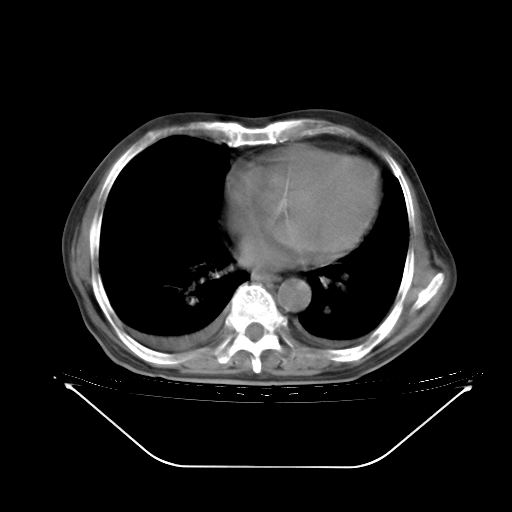

今天复查肺部CT,发现双肺广泛磨玻璃样改变。所以我把3月19日和5月9日相隔50天的肺部CT上传。请大家会诊。

5月9日肺部CT(在4月27日齐鲁医院肺部CT描述部分肺组织磨玻璃样改变,12天后肺组织广泛磨玻璃样改变)

2009年5月9日肺部CT